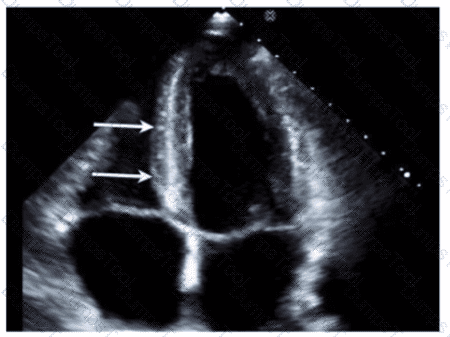

Which coronary artery territory is associated with the wall motion abnormality demonstrated in this video?